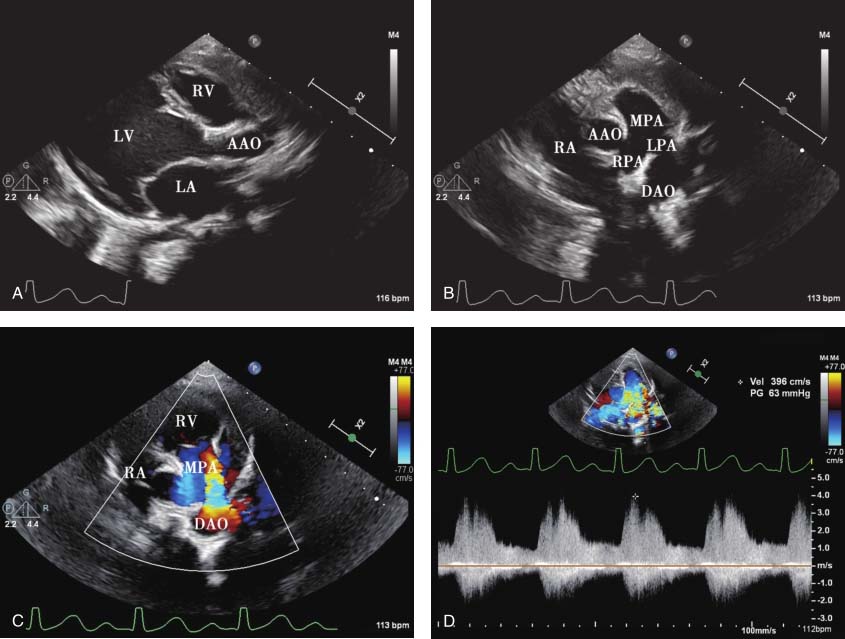

图15-1 患儿超声心动图表现

A.胸骨旁左心室长轴切面显示左心房、左心室内径增大,右心室内径正常;B.胸骨旁肺动脉长轴切面显示降主动脉与左肺动脉开口之间未闭的动脉导管,为管型,降主动脉侧和肺动脉侧内径相近;C.胸骨旁肺动脉长轴切面彩色多普勒显示降主动脉与左肺动脉之间左向右连续性分流信号;D.连续多普勒测量降主动脉与左肺动脉之间分流峰值流速为396cm/s,峰值压差为63mmHg;E.心尖四腔心切面显示二尖瓣环扩大,瓣叶对合缘减小;F.彩色多普勒显示二尖瓣中量反流;G.胸骨上窝切面彩色多普勒显示降主动脉与左肺动脉之间左向右连续性分流信号。

二维超声显示降主动脉峡部和左肺动脉之间导管回声,呈管样,主动脉侧与肺动脉侧内径相近。左心房、左心室内径增大,符合动脉导管未闭导致的左心前负荷增加的血流动力学改变。动脉水平为左向右高速连续性分流,连续多普勒测量分流峰值流速为396cm/s,峰值压差为63mmHg,据此计算肺动脉收缩压不高,患儿尚未出现肺动脉高压。由于左心内径增大,二尖瓣环扩大,导致二尖瓣叶对合缘减小,瓣叶对合不良,二尖瓣中量反流。最终诊断为动脉导管未闭(管型),二尖瓣中量反流。

动脉水平探及左向右连续性分流信号,峰值流速396cm/s,峰值压差63mmHg。二尖瓣中量反流,缩流颈宽约3.7mm。见图15-1。